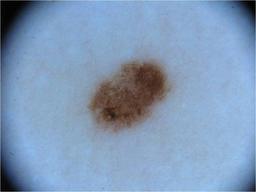

{

"age_approx": 55,

"anatom_site_general": "anterior torso",

"concomitant_biopsy": false,

"diagnosis_1": "Benign",

"diagnosis_2": "Benign melanocytic proliferations",

"diagnosis_3": "Nevus",

"diagnosis_4": "Nevus, Atypical, Dysplastic, or Clark",

"diagnosis_5": "Nevus, Dysplastic",

"image_type": "dermoscopic",

"melanocytic": true,

"sex": "female"